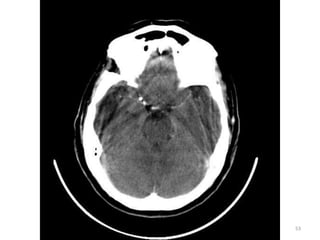

CORTES FOSSA POSTERIOR

81

SUPRA TENTORIAL

82

IMAGENS ÓSSEAS

83